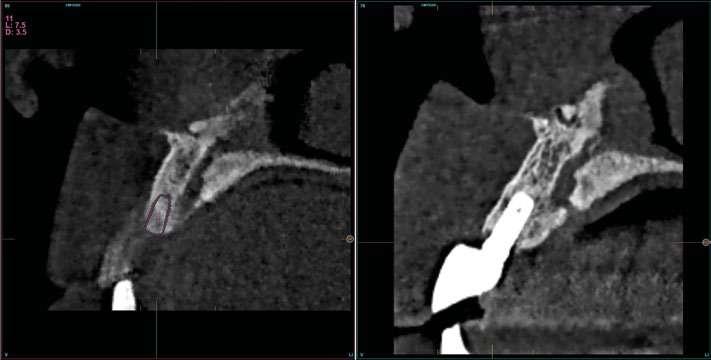

laterales se ponen de manifiesto aún más varias lesiones de esmalte que indican la parafunción en el paciente, unido a los desgastes excesivos en varias zonas (figuras 3 y 4). El paciente acude por dolor y movilidad en la pieza 11, que se ha incrementado en los últimos días, además de sensación de “diente crecido” que como podemos ver en las fotografías iniciales es real, ya que el diente se encuentra ligeramente extruido en relación con el contralateral. Estos signos parecen indicarnos una fractura o fisura. En la fotografía oclusal, podemos observar el desplazamiento del diente debido a la movilidad (figura 5). Posteriormente se realiza un sondaje positivo de la pieza, que lleva a 11 mm por lo que se confirma la sospecha de fractura y se procede a la exodoncia del diente, realizándose una regeneración posterior del alveolo con PRGF-Endoret y

esperándose 4 semanas hasta el cierre de los tejidos blandos y la neoformación ósea inicial para la colocación de un implante temprano. Cuatro semanas después, realizamos un cone-beam de control para conocer el estado del tejido óseo y poder planificar el implante. En el corte seccional observamos que se ha regenerado por completo el lecho receptor y tenemos un hueso óptimo para la inserción del implante, que por el tiempo transcurrido además es muy sencillo de expandir, con el propio implante generándose una expansión atraumática que nos permitirá ganar anchura ósea y con un implante estrecho de 3,5 mm de diámetro logramos posicionarlo sin dañar la desembocadura del nervio incisivo (figura 6). En cuanto a la longitud, con 7,5 es suficiente, no necesitándose un tamaño mayor para un correcto rendimiento biomecánico posterior.

Figura 6. Corte seccional de planificación del implante donde observamos el volumen óseo regenerado y la disposición del implante que se va a insertar por delante de la desembocadura del nervio incisivo.